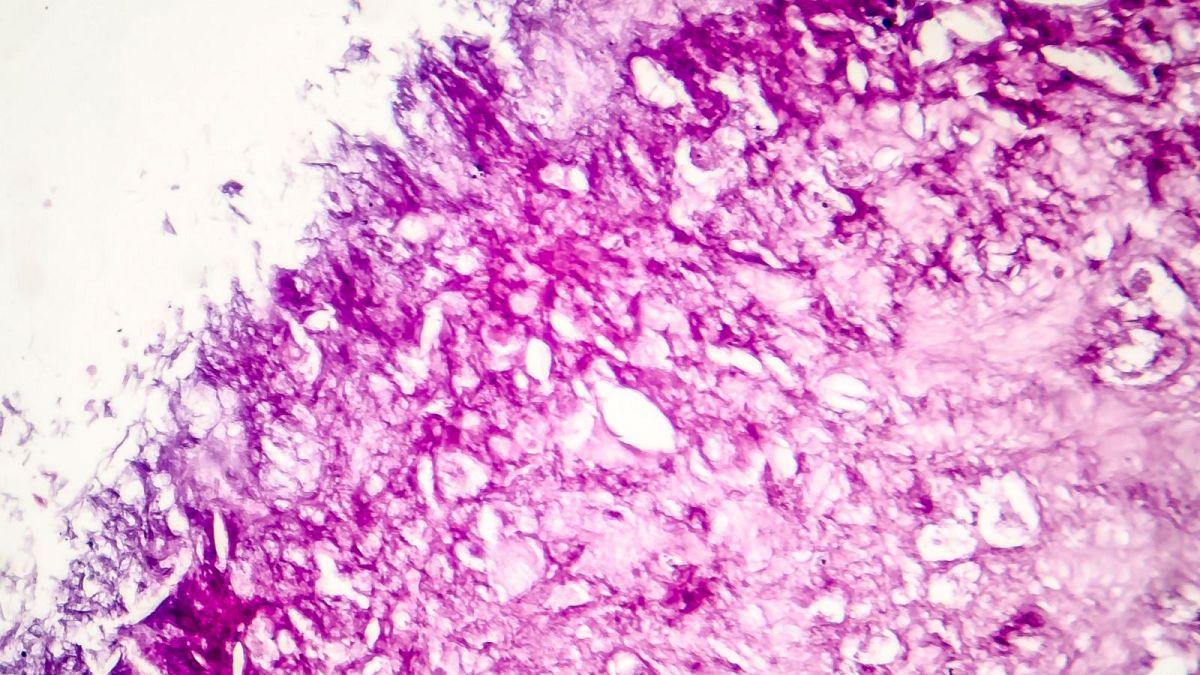

Selon les experts, la recherche à un stade précoce – qui a permis d’éradiquer 99 pour cent des cellules de mélanome en laboratoire – pourrait offrir de nouvelles options de traitement du cancer.

Les chercheurs ont découvert que la méthode était efficace à 99 pour cent contre les cultures en laboratoire de cellules de mélanome humain.